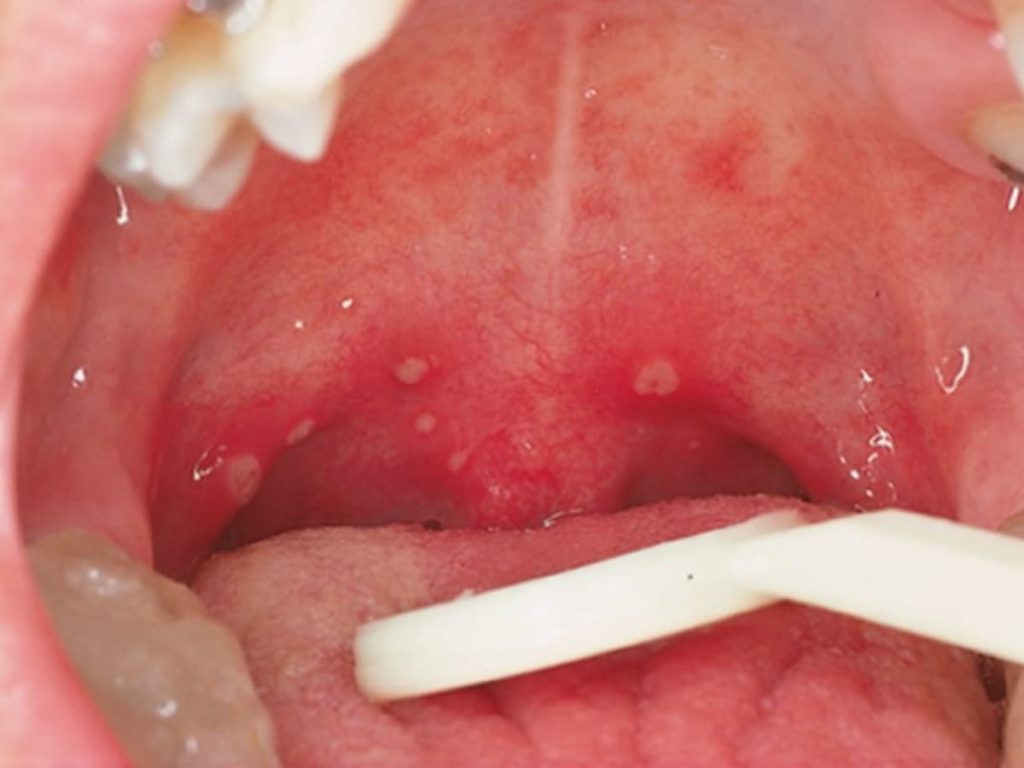

5. โรคเฮอร์แปงไจน่า (Herpangina)

โรคเฮอร์แปงไจน่า มักระบาดในช่วงฤดูฝน และพบบ่อยในเด็กอายุ 2 ถึง 10 ปี เนื่องจากเด็กยังไม่มีภูมิต้านทานของเชื้อนี้ โดยเฉพาะเด็กที่ไปโรงเรียนอนุบาล  มักเล่นของเล่นรวมกัน  หยิบจับสิ่งของรวมกัน  จึงมีโอกาสติดเชื้อได้ง่าย โดยตัวเชื้อจะอยู่ได้นานในอากาศเย็นและชื้น จึงระบาดมากในฤดูฝน แต่ก็สามารถพบได้ทุกฤดู โดยทั่วไปอาการไม่รุนแรง แต่อาจจะมีไข้เฉียบพลัน ไข้อาจสูงถึง 40 องศาเซลเซียส ปวดศีรษะ ปวดตามตัว อาจมีอาเจียน และอาการเด่นคือจะมีอาการเจ็บบริเวณเพดานปากและคอนำมาก่อน ต่อมา (ภายใน 1 วัน) จะมีจุดแดงๆ บริเวณเพดานอ่อน ลิ้นไก่ และอาจมีตุ่มแดงที่ทอนซิล หรือบริเวณในลำคอด้วยก็ได้ อย่างไรก็ตาม ไข้จะลดลงภายใน 2 – 4 วัน แต่แผลอาจคงอยู่ประมาณ 1 สัปดาห์

แต่ต้องระวังภาวะแทรกซ้อนที่สามารถเจอได้จากโรคนี้ ควรรีบนำเด็กพบแพทย์ เมื่ออาการไข้ไม่ลดลงภายใน 3 วัน หรือไข้สูง, รับประทานอาหารและดื่มนมไม่ได้ มีภาวะขาดน้ำ เช่น ปากแห้ง ปัสสาวะน้อยลง หรือมีอาการซึมลง